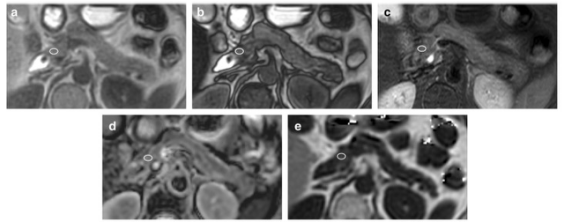

66 歲女性,胰腺正常組脂肪肝。 感興趣區域 (ROI) 的測量在胰腺頭部進行軸同相成像 (a)、軸反相成像 (b)、軸 T2 加權成像 (T2WI) (c)、軸表觀擴散系數 (ADC) 圖 (d) 和軸向多回波 3D DIXON (e)

本演技共納入了132 名患者,每位患者均接受了腹部 3-T MRI掃描。在正常胰腺實質測量中,計算了同相位圖像中的胰腺與肌肉信號強度比 (SIR-I)、反位圖中的 SIR (SIR-O)、T2 加權成像中的 SIR (SIR-T2) 、DWI 中的 ADC (×10-3 mm2/s) 和多回波 3D DIXON 中的質子密度脂肪分數 (PDFF [%])。將患者分為三組(正常胰腺組:n = 60,導管內乳頭狀粘液性腫瘤(IPMN)組:n = 60,IPMN-IC 組:n = 12)。